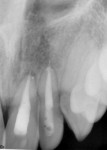

At presentation (Figure 1 through Figure 4), the patient was symptomatic with a dull ache. Teeth Nos. 8 and 9 were repositioned incorrectly, with tooth No. 9 being severely malpositioned. Upon examination, the patient was afebrile and alert and oriented times three. He stated that he did not lose consciousness at the time of the trauma. The patient’s vital signs were determined and considered normal. The patient had no history of significant medical disease, denied all medications, and had no known drug or food allergies. His review of systems was noncontributory for systemic disease. The patient’s head-and-neck examination exhibited no signs of facial fracture. A small laceration of his upper lip in association with tooth No. 9 was healing well. Teeth Nos. 8 and 9 were malpositioned, with tooth No. 9 being severely extruded. The remainder of his head-and-neck examination was unremarkable.

Teeth Nos. 8 and 9 were tender to percussion and palpation. Teeth Nos. 8 and 9 were nonresponsive to cold testing (Frigi-dent™, Ellman International, www.ellman.com). Teeth Nos. 8 and 10 were +1 mobile, while tooth No. 9 was +3 mobile. The gingival tissue around tooth No. 9 was erythematous. Periodontal probing depths were 3 mm to 4 mm generalized for all teeth except tooth No. 9, whose probing depths were 6 mm to 8 mm. Upon radiographic examination, teeth Nos. 8, 9, and 10 had widened periodontal ligament spaces. No other pathology was noted. The remainder of the examination was unremarkable.